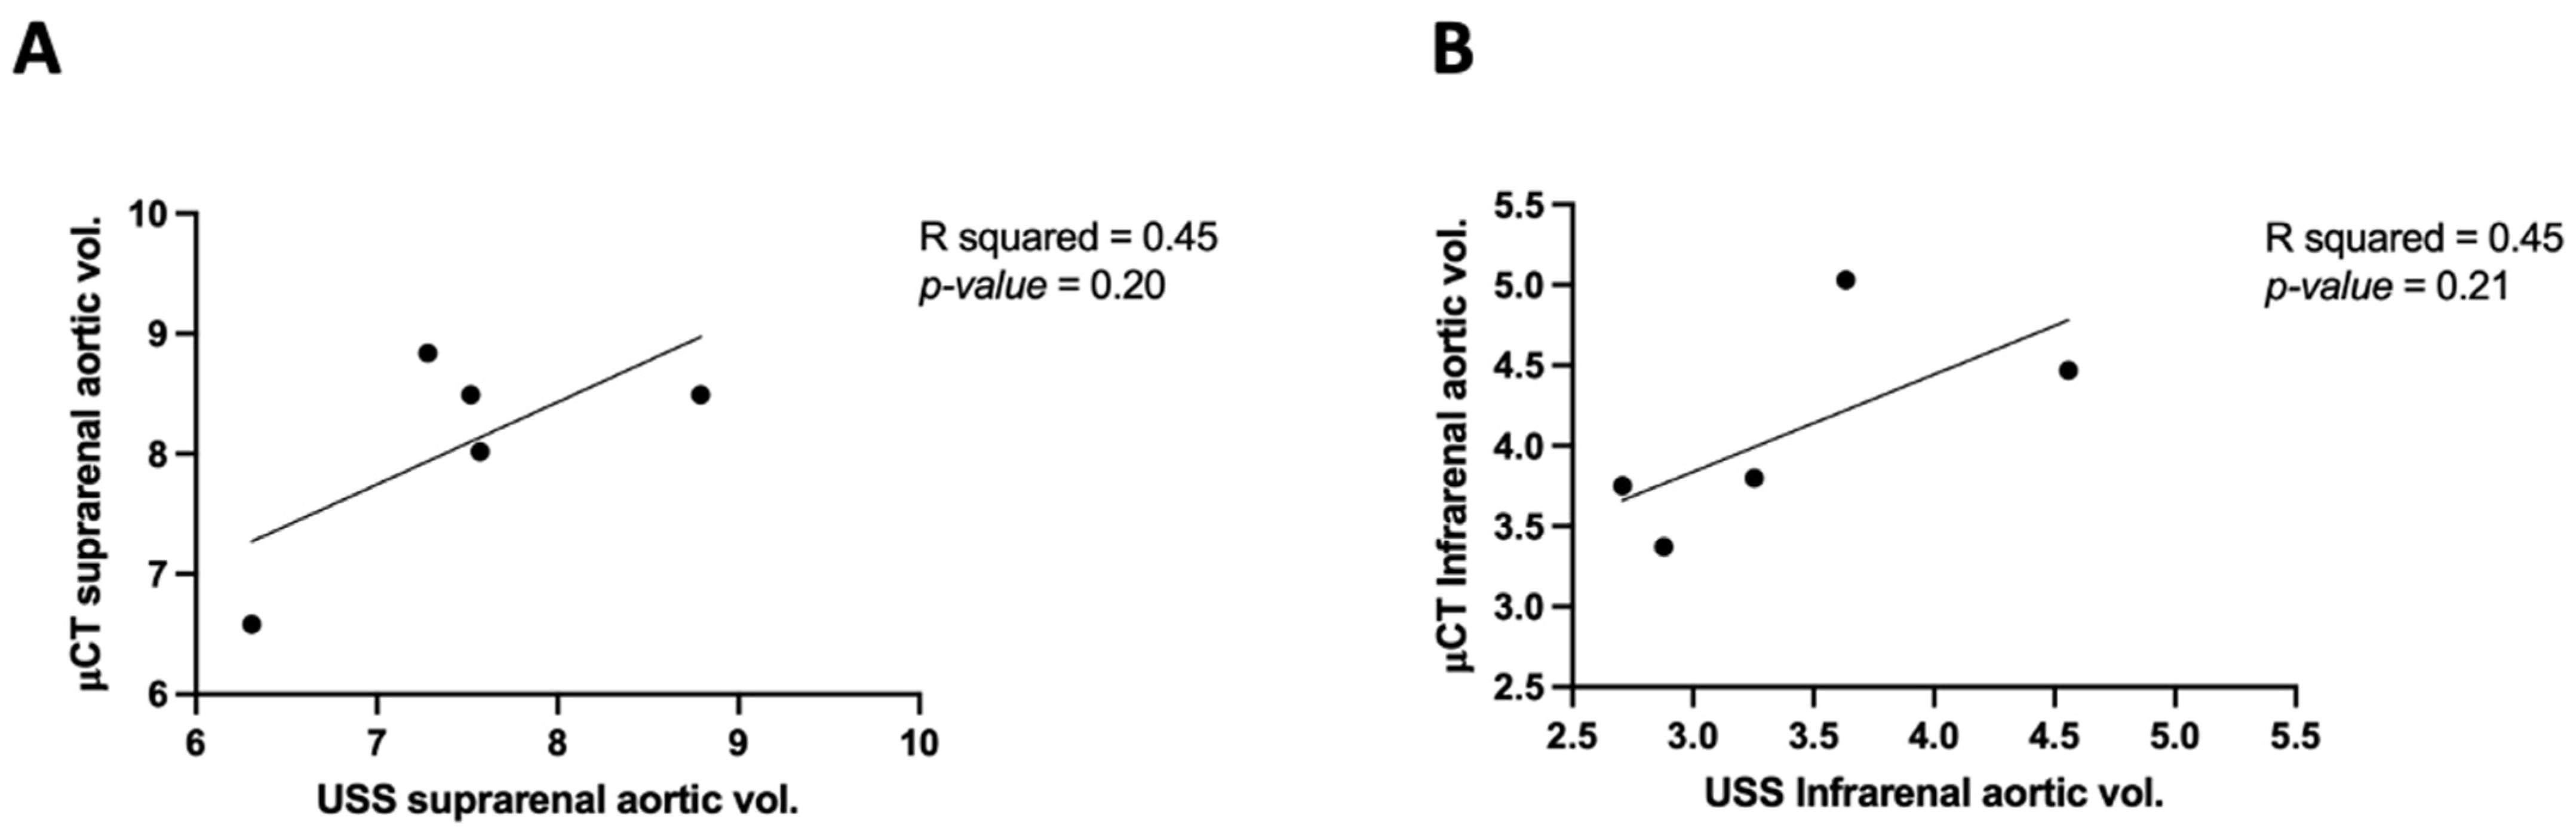

3.2. Comparing μCT and USS Aortic Measures

| Aortic volume | 7.57 | 3.254 | 8.02 | 3.8 |

| 7.52 | 4.558 | 8.49 | 4.47 | |

| 7.28 | 2.707 | 8.84 | 3.75 | |

| 6.308 | 2.879 | 6.58 | 3.37 | |

| 8.79 | 3.634 | 8.49 | 5.03 | |

| Mean ± SEM | 7.5 ± 0.39 | 3.4 ± 0.32 | 8.1 ± 0.39 | 4.1 ± 0.29 |